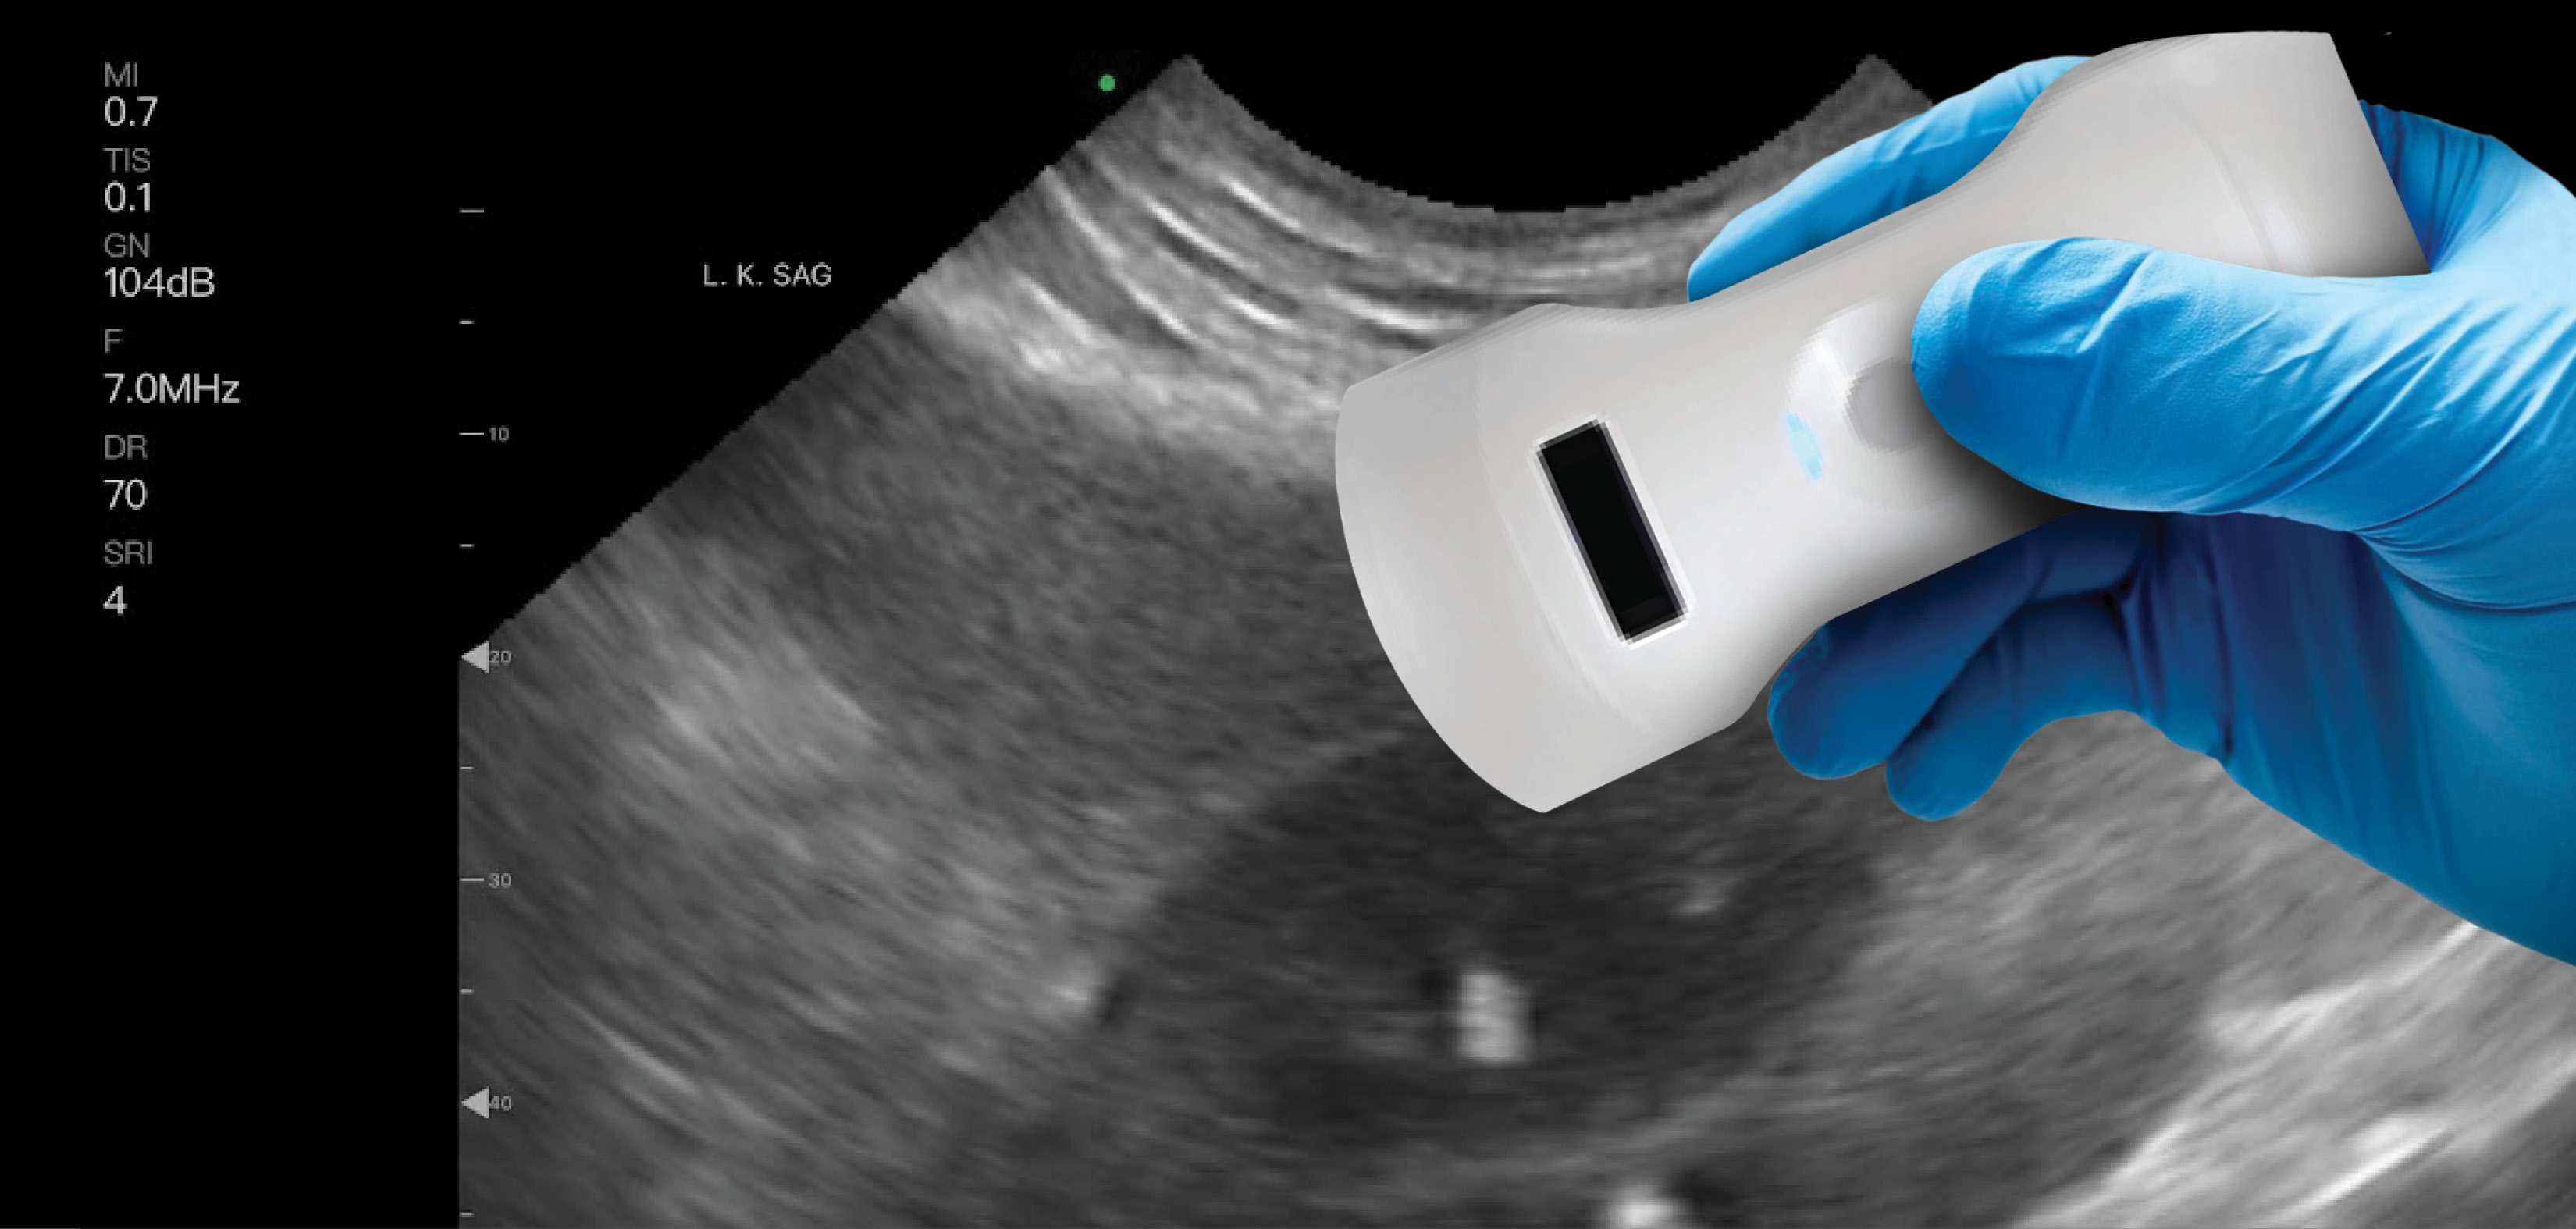

November 10, 2023 — MinXray Inc., a key global supplier of portable, compact digital imaging equipment, has added a line of wireless handheld ultrasound technology to speed diagnosis and improve triage efficiency in medical care.

The ultrasound units are designed to clear common obstacles that can prevent medical personnel from providing imaging services, such as affordability, portability and image quality. This is especially important for those who work in smaller clinics or more remote locations. A single probe can provide pulse wave doppler imaging for vascular analysis and guided procedures, as well as an obstetrics management package that includes gestational age and fetal weight estimation software at no extra cost.

Multiple probe models are available providing a wide variety of capabilities for individual clinic needs. Most come with multiple scan modes, giving doctors an array of imaging options with just one device. Units do not overheat and are both compact in size and waterproof. Some units also offer 3 hours of continuous battery life. These features combine to make these portable ultrasound probes durable for use in any condition.

In addition to making care more accessible, portable ultrasound does not come with any detriment to image quality. The new line of MinXray probes equals or exceeds most laptop-based and many cart-based systems in image quality for high levels of diagnostic accuracy and patient safety.